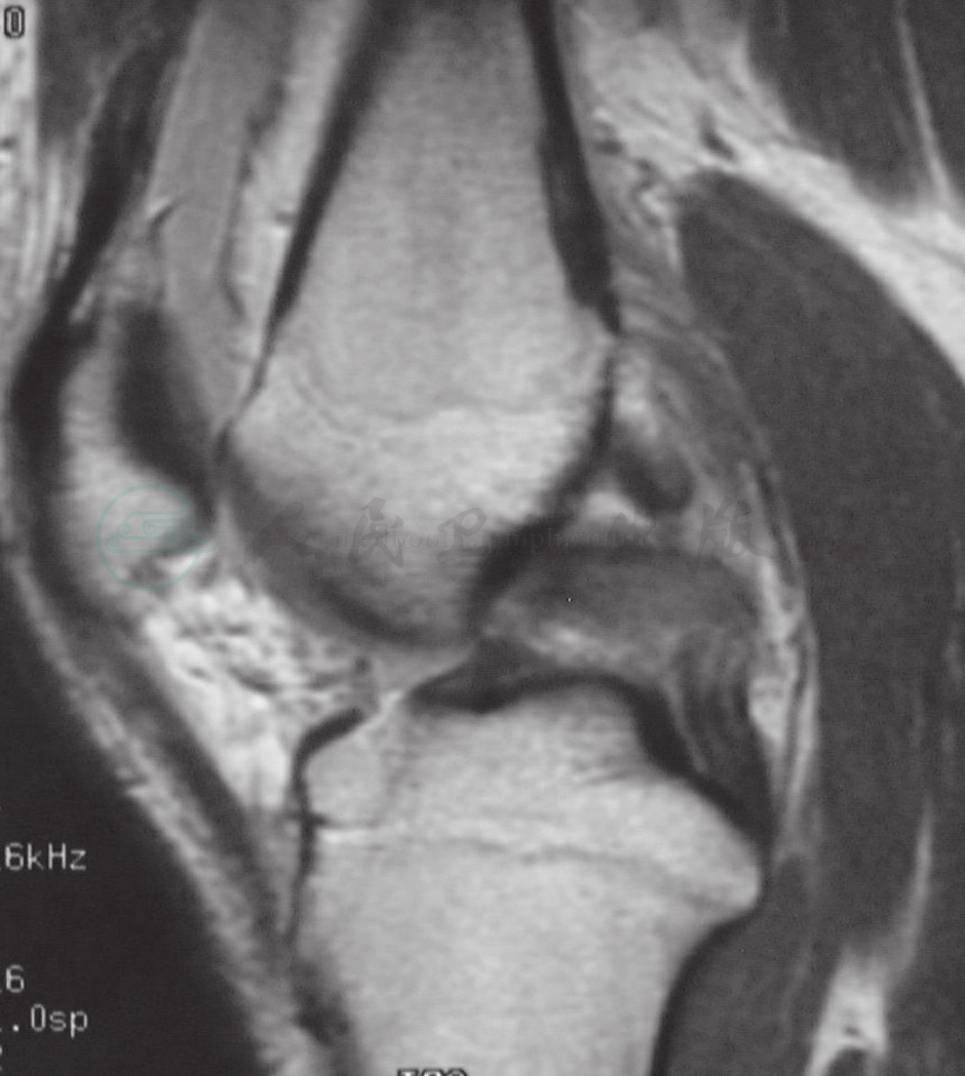

后十字韧带撕裂通常会被误诊,因为其临床症状轻微,甚至没有症状。其损伤机制通常为屈曲位胫骨近端前方受力所致,向后且合并内翻或旋转的外力可能会导致外侧或后外侧的联合损伤。另外一种导致单纯后十字韧带损伤的机制为膝屈曲着地的同时伴踝关节的跖屈。其他损伤机制包括极度过伸或过屈。单纯的后十字韧带部分撕裂或全部撕裂可以保守治疗,短期疗效良好,长期疗效尚有争议。后十字韧带的手术效果则很难说。最新的解剖和生物力学研究表明,手术重建适用于有症状的严重膝关节后侧不稳定或多韧带损伤。在考虑后十字韧带治疗方案的时候,要考虑以下因素:疼痛程度、不稳定程度、急性还是慢性损伤、MRI 检查结果、单一损伤还是复合损伤、患者生活方式是积极的还是消极的等等(图2)。

图2 后十字韧带撕裂MRI检查